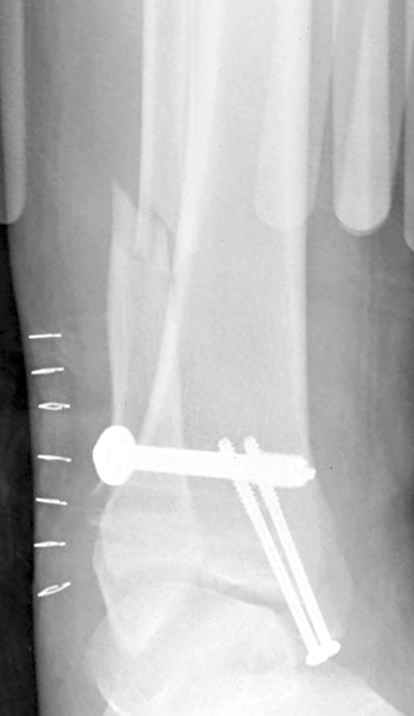

12 января прямой

|

12 января боковой

12 января трехчетвертной

Риторический вопрос - в каком руководстве рекомендован такой способ остеосинтеза наружной лодыжки?

Очевидно, такой результат операции был запрограммирован. При невосстановленной длине и практически нефиксированной малоберцовой кости (этот кортикальный винт - как карандаш в стакане), при неустраненном подвывихе, невправленной и тоже нефиксированной внутренней лодыжке нет стабильной вилки сустава. Если такую операцию сделать даже сразу, а не через 4 месяца, то результат ожидаем

тот же.